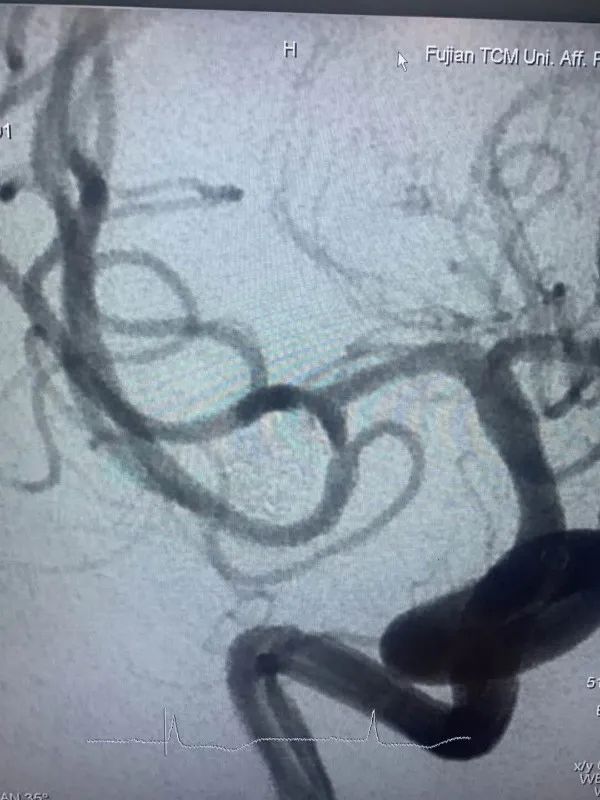

近日,省人民医院神经外科为一位高龄动脉瘤患者施行了介入治疗,成功栓塞了破裂的大脑中动脉瘤。患者因突发晕厥后头痛不适入院,急诊行颅脑CT检查提示蛛网膜下腔出血,行颅脑CTA检查后证实患者存在右侧大脑中动脉瘤。患者高龄,既往基础病多,高血压病、糖尿病、冠心病、双侧颈动脉硬化、双侧腹股沟疝术后等,手术风险较大,经家属签字同意后,当日急诊全麻下行“右侧大脑中动脉瘤介入栓塞术”,术中见血管迂曲明显,导管到位艰难,经过努力,手术顺利结束。术后予多次腰椎穿刺术释放血性脑脊液,患者头痛头晕症状渐缓解。患者住院治疗10天后顺利康复出院,未留后遗症。

动脉瘤主要有两种治疗方式:开颅手术和介入栓塞。两种方法比较,介入栓塞手术时间短、康复快、不需开颅、可同时治疗多个动脉瘤,适合高龄、分级高的患者,其中血管内弹簧圈栓塞术是颅内动脉瘤最常见的一种介入治疗方式,随着介入新材料、技术的不断进步,介入栓塞的优势日渐明显。